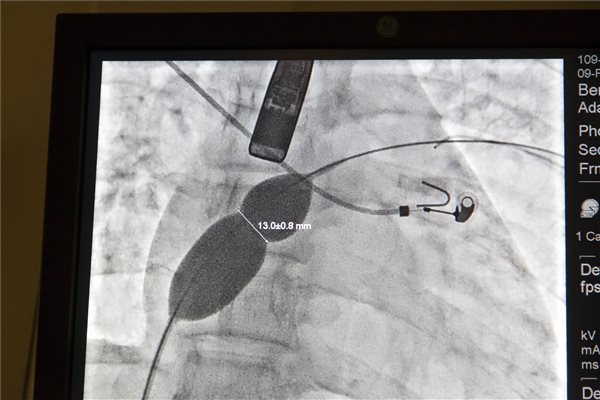

Az egyik leggyakoribb veleszületett szívrendellenesség, a bal és a jobb pitvar közötti nyitott sövényt katéteres beavatkozással is korrigálni tudják már a Zala Megyei Szent Rafael Kórházban

Lupkovics Géza, a kardiológia osztályvezető főorvosa a műtéti eljárás részleteit ismertetve azt mondta: az egyik leggyakoribb veleszületett szívrendellenesség, a pitvari sövény hiánya 100 ezer ember közül négyet érint Magyarországon. Ha nem fedezik fel és műtik meg időben, akár már gyermekkorban, akkor az egyébként tünetmentes páciens néhány évtized után szívelégtelenségben fog szenvedni.

A sajtótájékoztatóval egy időben négy műtétet hajtottak végre a zalaegerszegi kórházban, a páciensek 19 és 45 év közöttiek voltak. A műtét fél-egy órát vesz igénybe komplikációmentes esetekben, s ilyenkor a páciens már másnap hazatérhet a kórházból.

A főorvos kifejtette: tavaly év vége óta végeznek nyitott szívműtét helyett ilyen katéteres eljárást a "lyukas" szív korrekciójára, s az eddigi tapasztalatok alapján a betegek jelentősebb szövődmény nélkül gyógyultak meg.